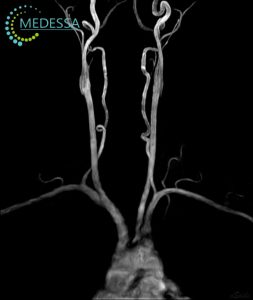

МРТ – найефективніший метод дослідження стану мозку. Він не лише безпечний і неінвазивний, а й надає детальну та точну інформацію, без впливу шкідливого опромінення, на відміну від рентгену чи КТ. МРТ голови дозволяє оцінити всі структури мозку, включаючи судини, мозкові оболонки та нервові корінці.

Для виявлення навіть незначних змін застосовуються 3D-послідовності та зрізи з високою роздільною здатністю.

Як результат, лікар отримує максимально точну інформацію про патології на ранніх стадіях, включаючи пухлини, за короткий час. Загальний час сканування голови без контрасту займає близько 10-15 хвилин.